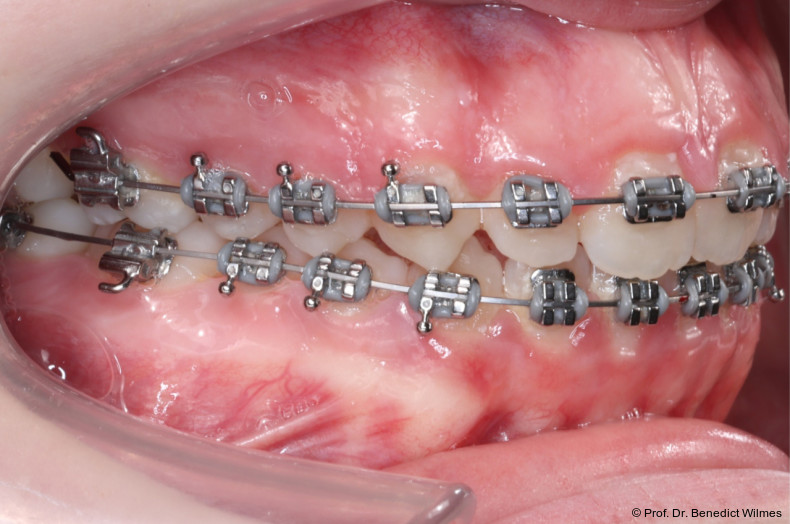

Nach erfolgreicher Expansion und Molaren­intrusion wurde eine Multibracket-Therapie zur Ausformung und Koordination der Zahnbögen durchgeführt (Abb. 8a–f). Nach Abschluss der aktiven Behandlungsphase wurden die Apparaturen entfernt und festsitzende Retainer im Ober- und Unterkiefer eingesetzt (Abb. 9a–k).